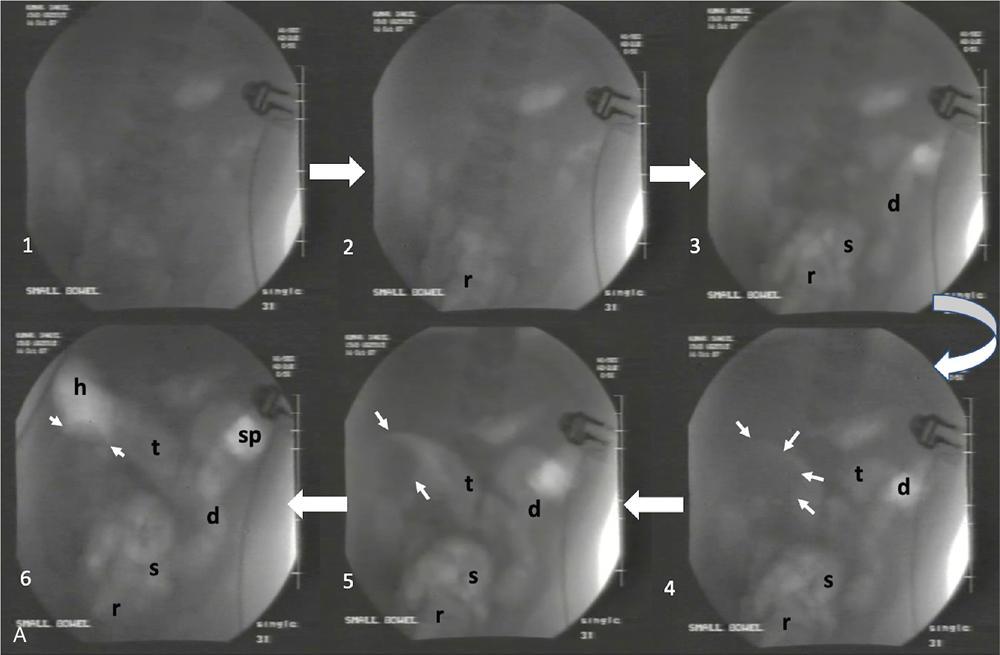

Ajay Taranath, Lino Piotto Intussusception is a common cause of acute abdominal pain in children. In this condition, a portion of the bowel wall, the intussusceptum, invaginates into the lumen of the portion of the bowel immediately distal to it, the intussuscipiens. It occurs most commonly in the first two years of life but is sometimes seen in older children. Once the invagination process has begun, the first part of the intussusceptum (the head) is pushed distally by peristalsis dragging the wall of the bowel with it. This tends to be progressive once it starts and as the invagination continues, interference with the blood supply of the intussusceptum causes venous occlusion and subsequent mucosal congestion. In advanced cases, the vascular compromise may result in the passage of blood-stained mucus through the rectum (red-currant jelly). Intussusception may be idiopathic or may be due to a pathologic ‘lead point’ such as a Meckel’s diverticulum, duplication cyst or neoplastic mass within the bowel wall. Most patients under the age of 2 years are in the idiopathic group. These are thought to be associated with thickening of bowel wall caused by hyperplasia of Peyer’s patches in response to a recent viral infection. Pathologic lead points are much more common in patients older than 4 years. For this reason, the head of the intussusceptum in these patients should be scanned carefully for evidence of a lead point. Intussusception is usually described according to the bowel that is involved. Those involving only small bowel include jejuno-jejunal (jejunum into jejunum) and ileo-ileal (ileum into ileum), are often seen as an incidental finding in abdominal sonography and only infrequently require intervention, when they have caused a bowel obstruction (Fig. 7.12.1A and B). Those involving large bowel include ileo-colic (ileum into colon), ileo-ileo-colic (ileum into ileum and then into colon) and colo-colic (colon into colon) and almost always require intervention. The most common of these is the ileo-colic type, in which the terminal ileum invaginates the colon through the ileo-caecal valve. The longer the intussusception persists, the greater the likelihood of gut necrosis and the need for surgical resection. Typically, children with intussusception will present with some or all of the following clinical features: attacks of colic, vomiting, blood and mucus per rectum, palpable abdominal mass. The attacks of colic are often associated with drawing-up of the legs. The duration of symptoms is usually less than 48 hours. The peak incidence is around 18 months though it can occur in children as young as 5 months and as old as 15 years. Traditionally, children suspected of suffering from an ileo-colic intussusception would be investigated with supine, erect and occasionally prone plain radiographs. When the clinical suspicion was high, the only way to confirm or exclude the presence of an intussusception was to perform a barium enema. A hydrostatic reduction using barium would then be employed to reduce an ileo-colic intussusception if one was found. More recently, pneumatic reductions have become the method of choice in many departments; benefits of this method include excellent reduction results and less radiation exposure than a barium enema. Pneumatic reductions have also shown to have greater reduction success rates than with barium. However, depiction rates of a pathological lead point on air enema are poor. Navarro et al. demonstrated a depiction rate of 11% in their study. Miller et al. showed a slightly higher depiction rate of 16%. Also, it must be noted that a successful reduction by an air enema cannot exclude a pathological lead point. In particular, lesions within the small bowel can be overlooked. Reduction rates also diminish when a pathological lead point is involved. Navarro et al. achieved a reduction rate of 29% in children presenting with their first episode of intussusception resulting from a pathological lead point. The relatively high-radiation dose from enema reductions was a significant factor in the development of ultrasound techniques, initially used only to identify those patients who had intussusception and therefore required a reduction. As a natural progression, the use of ultrasound in some institutions has been extended to monitoring of the reduction procedure. It is very important that the patient is well hydrated. It would be beneficial to have an intravenous access in all the patients with ileo-colic intussusception needing a pneumatic reduction. Administration of antibiotics may need consideration to ward off complications that might arise if there was an inadvertent perforation. It would be helpful to administer analgesics in consultation with the surgical team to help obtain compliance. The paediatric surgeon is in attendance. An 18 g cannula is kept handy to release the free air if a perforation occurs during the attempted reduction. The setup for a pneumatic reduction of intussusception (Fig. 7.12.2) consists of the following: (i) A cylinder of sterile medical air. (ii) A tube that leads away from the cylinder to a pressure limiting chamber. It has a dial indicating the pressure and a valve at the top of the chamber that will open if the pressure attained intraluminally goes over what has been set. (iii) A tube leading from the pressure-limiting chamber to a Foley’s catheter that is placed in the rectum. (iv) A three-way Y-valve (that can be controlled by the operator’s thumb in case the pressure control needs to be achieved quickly) is interposed midway in the tube leading out of the pressure chamber. It is important to get a good seal at the rectum. The chamber pressure is set at 80 mm Hg at the start of the reduction. A thumb rule of 3 is followed in that if there is no success with reduction after employing a pressure of 80 mm Hg for 3 minutes, it is increased to 100 mm Hg for 3 minutes and if the operator is comfortable, to 110–120 mm Hg for 3 minutes. If reduction is not achieved, surgical intervention may need to be considered in consultation with the paediatric surgeons. The air insufflation is begun. Retrograde movement of the intussusceptum is tracked fluoroscopically. There may be a point when the intussusceptum reaches the ileo-caecal junction and fails to respond to the air insufflation. It would helpful for the patient as the ileo-colic intussusceptions without pathological lead points tend to reduce, albeit in a delayed manner. The procedure is concluded when the insufflated air enters the small bowel loops (Fig. 7.12.3A and B).